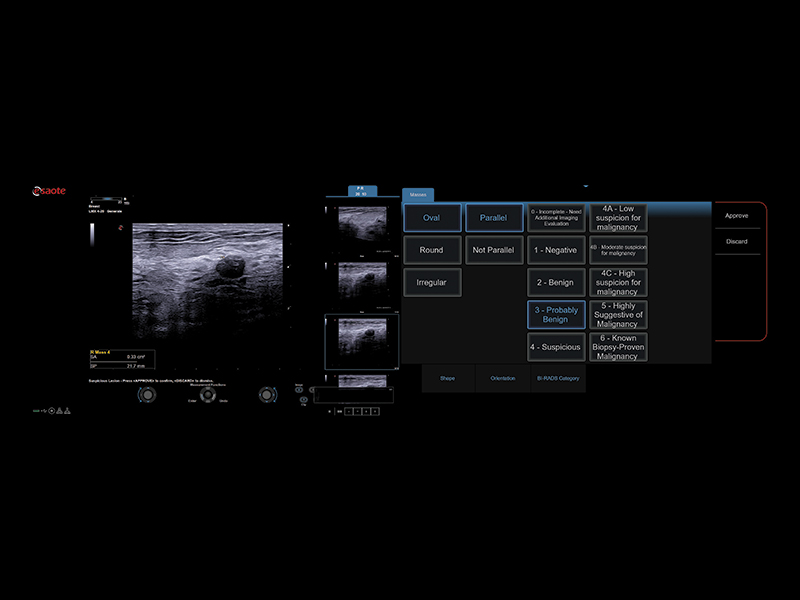

A.I.-based technologies for automatic lesion characterization

Driven by Artificial Intelligence, Esaote’s solutions in breast ultrasound imaging open new horizons in early detection and help to provide reliable evaluation of suspect areas.

Breast Mass Analyzer (BMA), powered by A.I., is a machine learning model based on radiomics to predict the BI-RADS® category of ultrasound-detected suspicious breast lesions, support medical decision-making and reduce unnecessary biopsies. The A.I.-based eDetect algorithm provides automatic contouring of breast lesions and automatic measurements (P & A) of suspect areas. It also provides automatic cross-distance measurements of the lesions.

Comprehensive BI-RADS® Report

All Esaote systems include a complete, dedicated report template, produced according to the BI-RADS® scoring/guidelines, with lesion description, main characteristics, and a graphic representation (body map) of their positions.

The optimized workflow guarantees easy and fast computation through the touchscreen or the worksheet page.